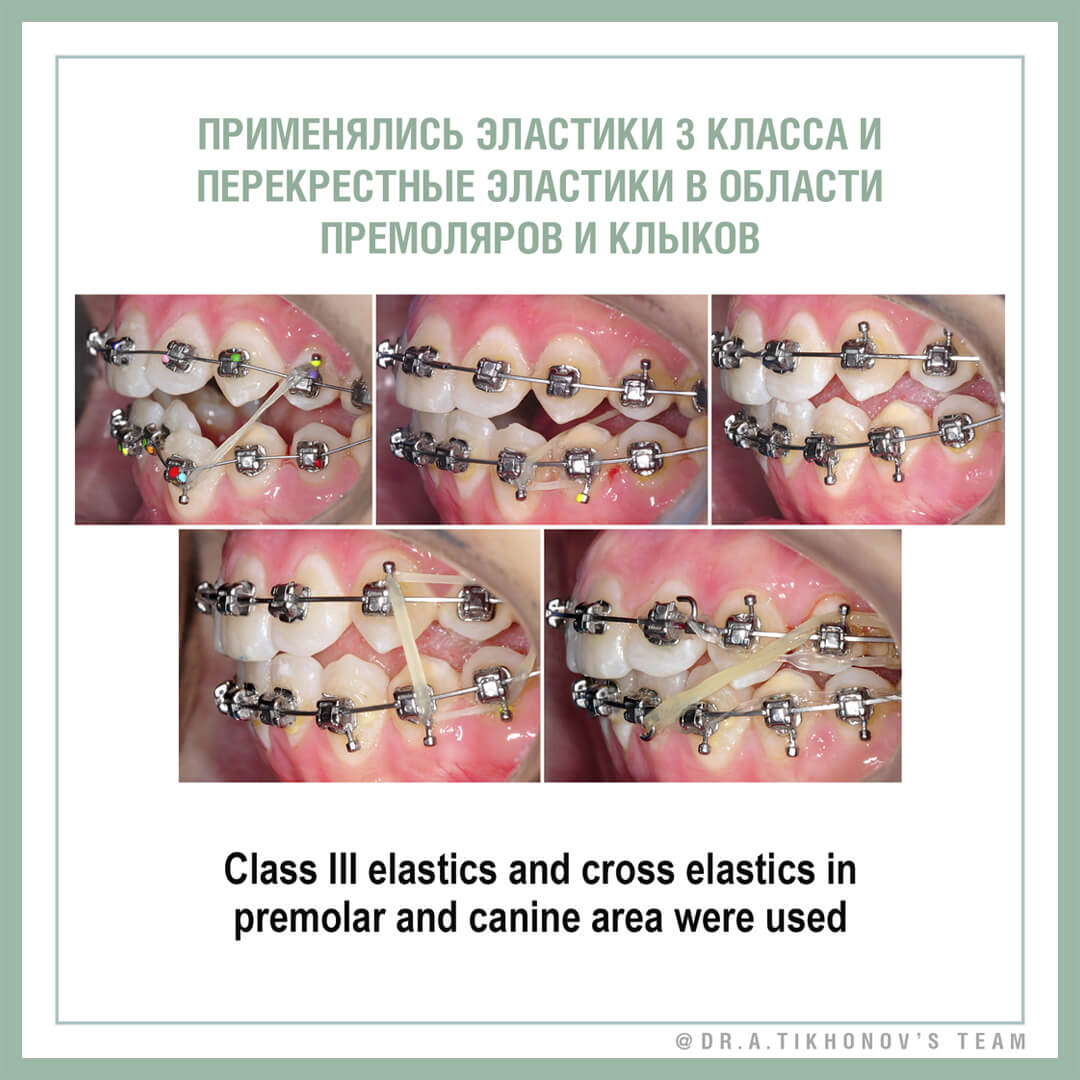

После сильного расширения возникнет много лишнего места и придется еще больше мезиализировать верхние моляры, чтобы поставить их во 2 класс (нет верхних премоляров). Или тогда ставить имплантаты в области 5, да еще дистализировать моляры, удалив мудрых малышей. Если же броситься исправлять сужение верха без хирургии, то или верхние моляры выйдут из кости в знак протеста, или мы их сильно наклоним, получив интерференцию на небных буграх и тенденция станет вполне открытым прикусом.

I think, it’s not possible to fully correct cross bite without SARPE in traditional way (while MARPE in adults is still experimental option). If we try to correct by dentoalveolar movement, the molar roots will be out of bone or crowns should be tipped buccally with «hanging» palatal cusps and bite opening due to premature contacts. If we expand with SARPE, too much space will be created, that will lead to longer treatment to mesialize upper molars. The second option is to create space for Implants after expansion and distalization, that is also not perfect.